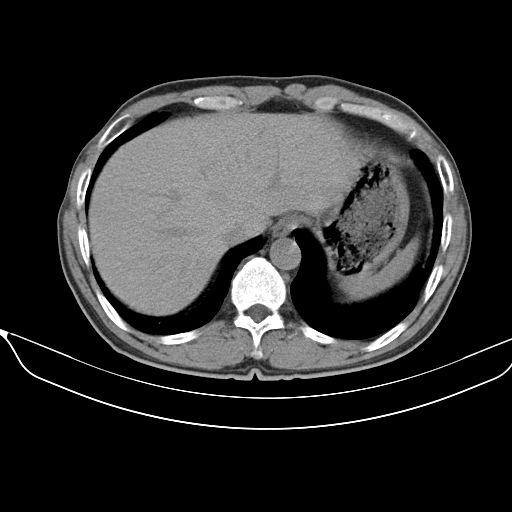

以下是引用shuiyuan在2010-3-1 10:45:00的发言:[br]考虑左肺上叶中心型肺癌伴阻塞型炎症,邻近胸膜受侵。